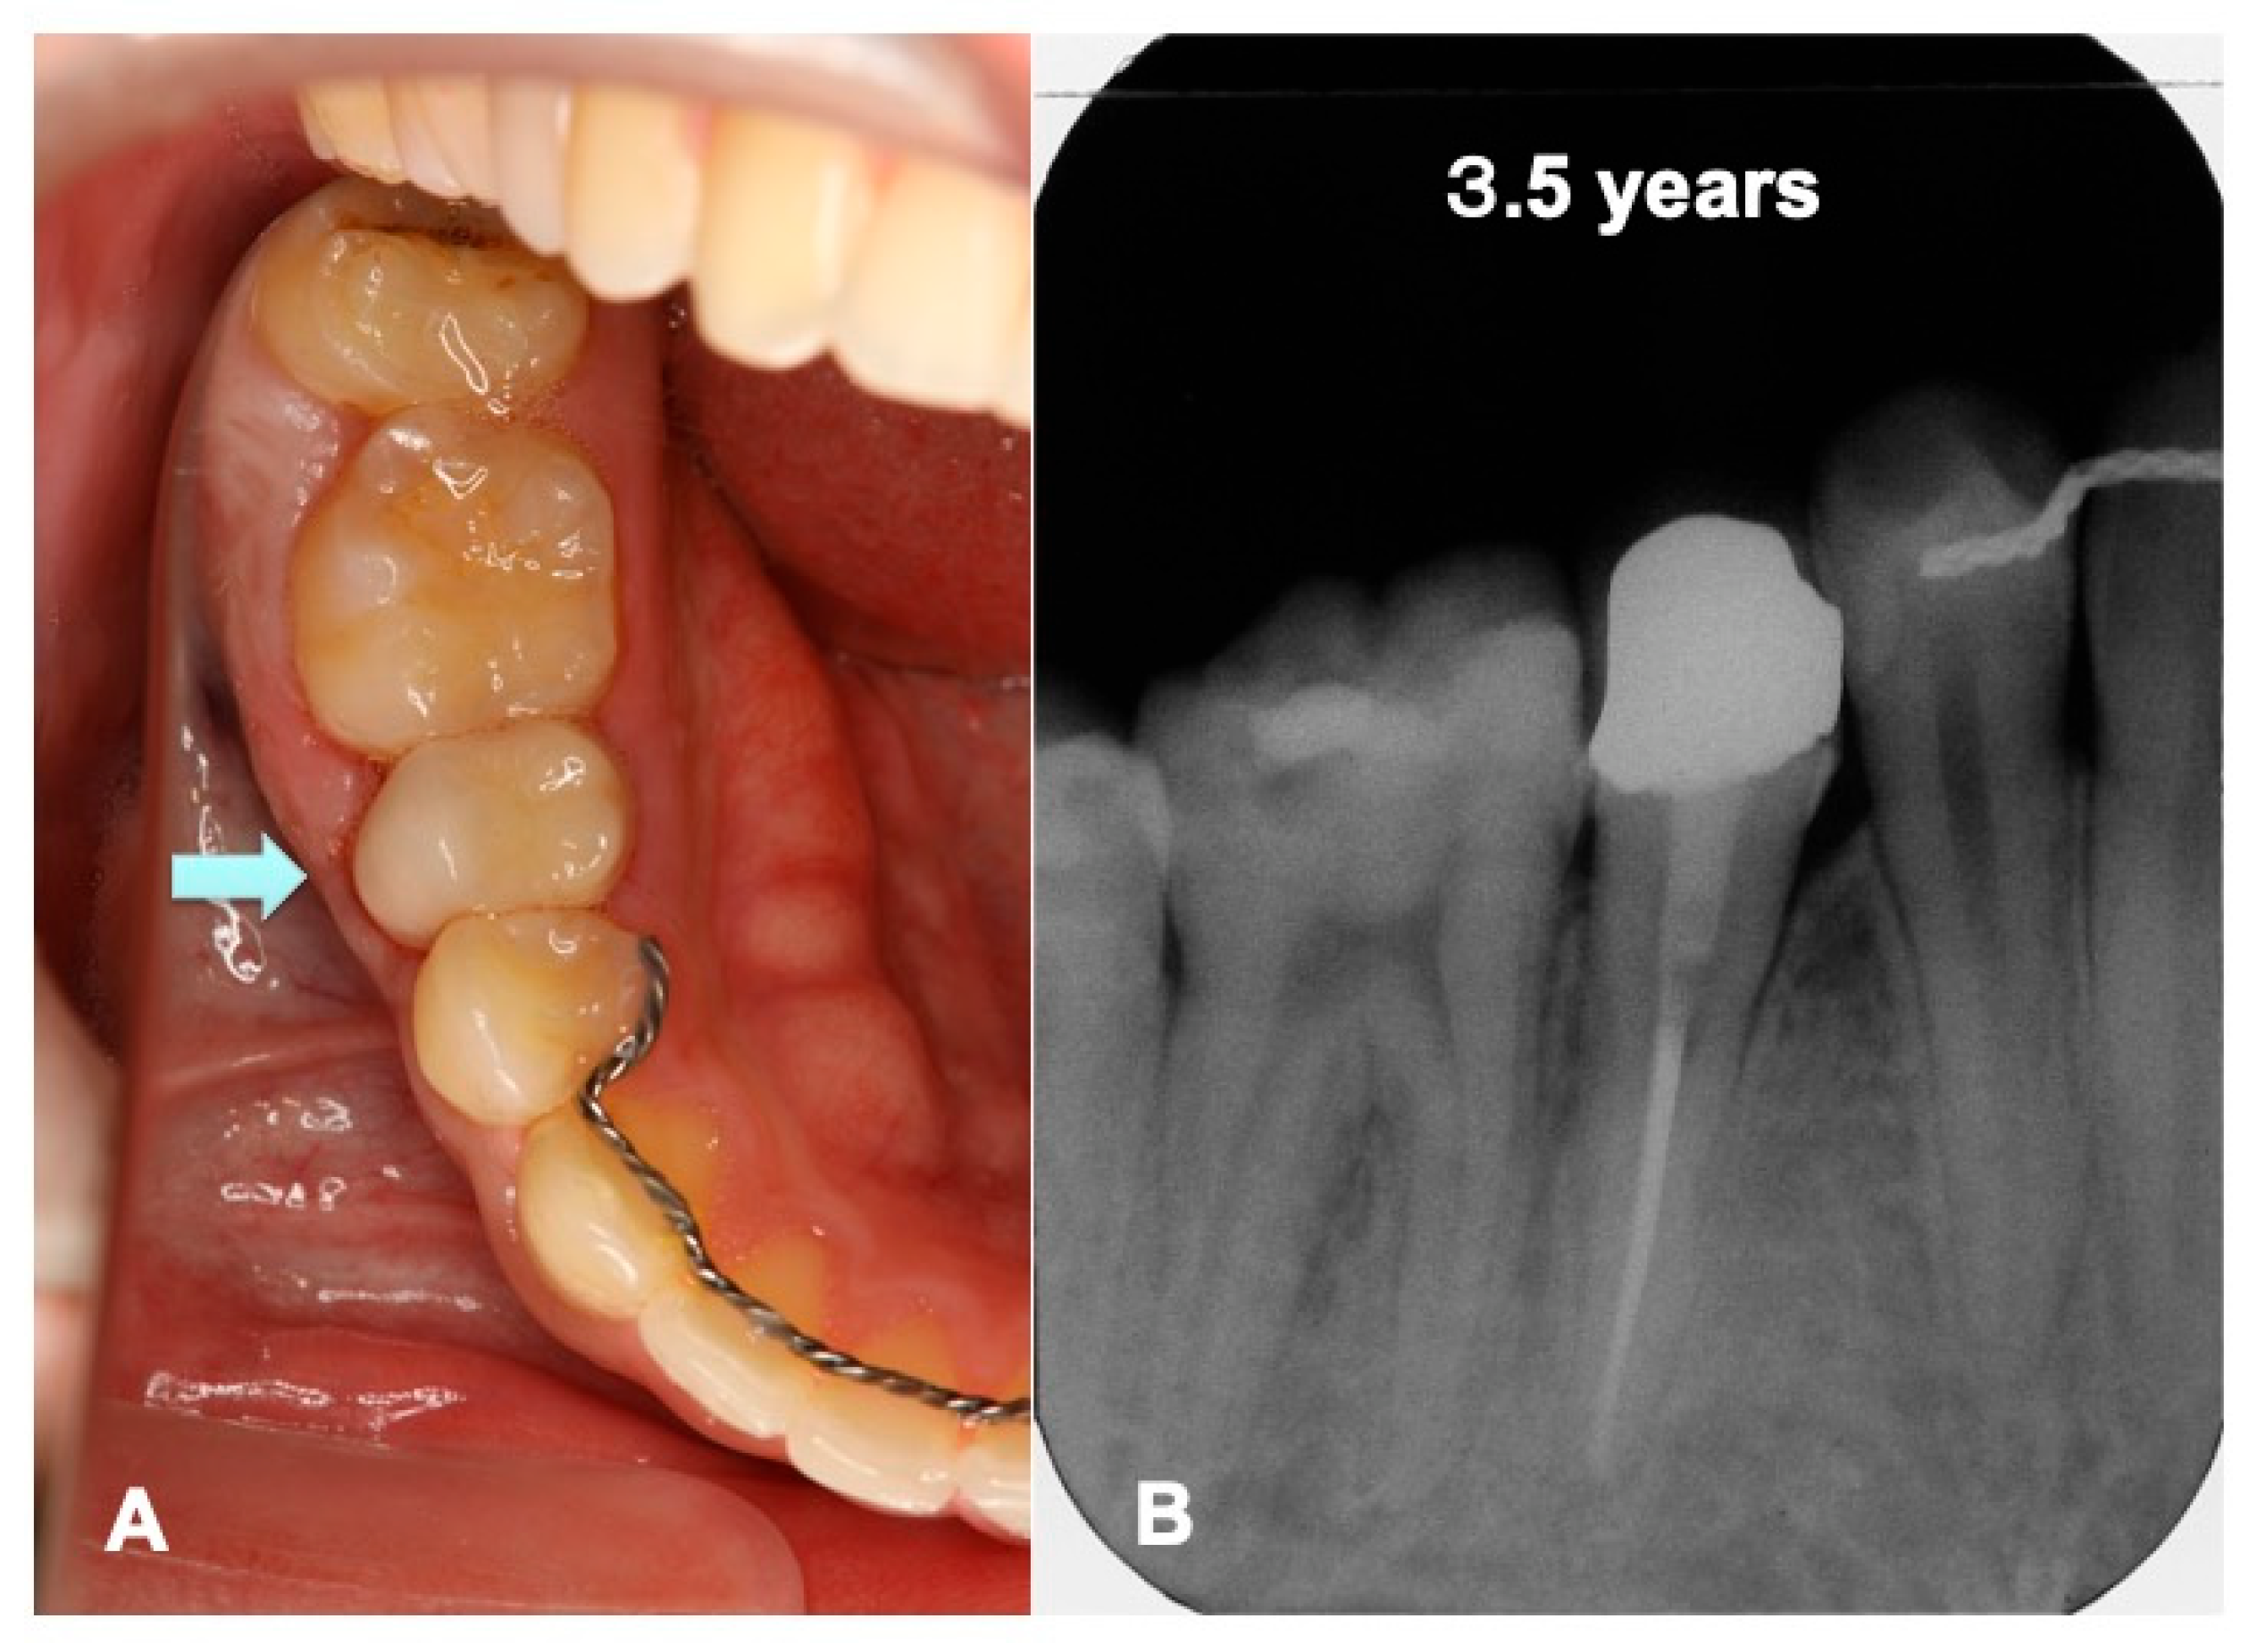

Figure 8.

Set of partially veneered zirconia all ceramic crown (Nobel Procera®, Nobel Biocare Co., Ltd., Zurich, Sweden) rutted using adhesive resin cement (RelyX Ultimate®, 3M ESPE Co., Ltd., Seefeld, Germany) in 2015. (A) Mirror view just after final crown set. Arrow indicating biological gum line (#45). (B) X-ray photo showing continuous periodontal ligament space indicating non-ankylosis. Healthy bone-like shadow with lamina dura (#44–46) at recall follow-up after 3.5 years.

Just after the surgery, the extracted sockets of the maxillary premolars and the root canal filling of the transplanted tooth were seen clearly (Figure 6A). The grafted pDDM were confirmed as each radiopaque granule (Figure 7A). The transplanted root and bone showed a similar radio-opacity, and a periodontal ligament space was not seen (Figure 6A). After 1.5 year of orthodontic treatment, the periodontal ligament space and alveolar ridge line were observed, and pDDM granules were not seen clearly (Figure 6B and Figure 7B). In addition, all wisdom teeth were already extracted (Figure 6B). A slight curve of the root surface was observed adjacent to a normal periodontal ligament space and the lamina dura during the orthodontic treatments (Figure 7B). The view at 2.5 years shows removal of orthodontic devices, except the mandibular retention wire, and a single standing of the transplanted tooth without wire (Figure 6C and Figure 7C). A continuous periodontal ligament space and lamina dura were found, and root concrescence did not occur (Figure 7C and Figure 8B).

4.5. Dentin/Cementum as a Biological Graft Material